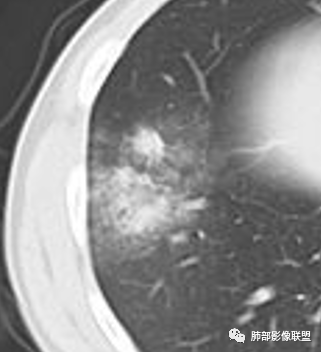

从图像上看病灶是外周起步,呈磨玻璃影,小叶核心区域,并见腺泡结节融合实变,后期发展迅速,可见小网格及小叶内间质增厚,首先考虑病毒感染,感觉病灶的起步更像些病毒,支原体带排。

大家再看看周围的病灶,进展时细网格还是很明显吧

以小叶为单位向周围明显进展,累及间质尤其是小叶内间隔为主。

但是分布是胸膜下,周围重,内带轻。符合间质来源

这是一些散在分布的小叶内核心区域结节影。

外围分布为主且边界不清的毛玻璃影、小叶间隔和小叶内间隔增厚(大网格征和细小网格)、小叶核心结节、支气管血管周围间质增厚

边缘模糊小叶核心结节,常多发